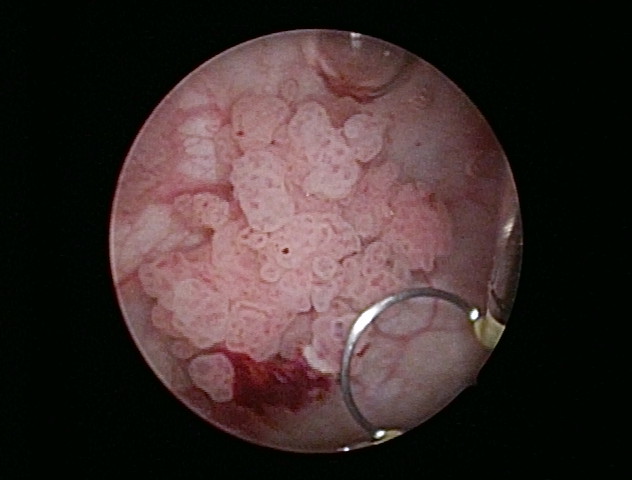

膀胱癌の内視鏡所見(切除に使用するループも観察できる。)